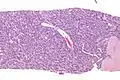

Micrograph of an adenomyoepithelioma. H&E stain.

An adenomyoepithelioma of the breast is a rare tumour in the breast composed of glandular elements (adeno-) and myoepithelial cells. It is usually benign;[1] however, there are reports of malignant behaviour.[2]

The histomorphologic appearance can mimic invasive ductal carcinoma, the most common type of invasive breast cancer.